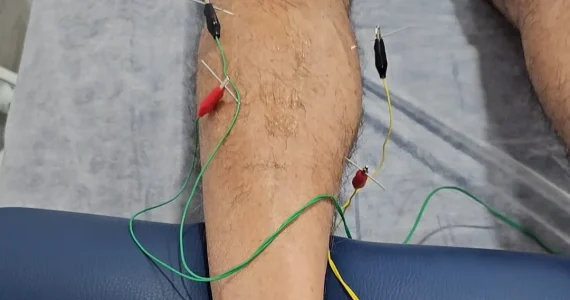

Punción seca

Técnica fisioterapéutica invasiva que utiliza agujas finas de acupuntura para tratar puntos gatillo miofasciales, que causan dolor y disfunciones musculares. Se denomina “seca” ya que no introducimos ningún medicamento con la aguja. El efecto que tiene la aguja sobre el músculo es mecánico, alivia el dolor y mejora la función muscular, aumenta el rango de movimiento, reduce la inflamación y acelera la recuperación.

Neuromodulación

Técnica invasiva que utiliza agujas para estimular puntos neuro reactivos del cuerpo mediante una corriente de baja frecuencia. Modula la actividad del sistema nervioso y mejora el control neuromotor, reduce el dolor y acelera la recuperación de la lesión.

EPTE

La electrólisis percutánea terapéutica es un tratamiento que utiliza una corriente galvánica a través de una aguja para tratar lesiones en tejidos blandos como roturas musculares o tendinopatías.